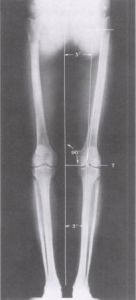

準確地理解和建立精確的下肢對線是人工膝關節置換術的最基本也是最重要的概念。脛股角是股骨解剖軸線與脛骨解剖軸線在膝關節中心相交形成的向外側的夾角,此夾角平均為174°。

在正常的生理情況下,當人體站立位時,股骨頭的中心、膝關節的中心及踝關節的中心應處乾同一條直線,此直線即為下肢的力學軸線或稱機械軸(mechanicalaxis):且此時經膝關節平面的水平軸(transverseaxis)則應與地面相平行。經股骨幹的股骨解剖軸與上述下肢機械軸在膝關節中心相交形成平均約為6°的外翻角,根據股骨頸乾角和股骨頸及股骨幹長度的不同,此角度可能會有變化。正確地認識和理解股骨解剖軸與下肢機械軸及其角度的意義對於在膝關節置換術中重建正常的對線是至關重要的。(圖示)

02在病理情況下,由於膝關節的內/外翻,正常的脛股角將發生變化,而下肢的機械軸將不可能通過膝關節的中心,這正是我們在膝關節置換術的術前計畫和手術中需要通過測量和截骨解決的問題。通過計算和測量準確的截骨才能使下肢力線獲得正確的重建。下肢力線的重建是確保手術成功的關鍵,也是避免術後因應力不均而造成鬆動的重要環節。

圖示下肢對線